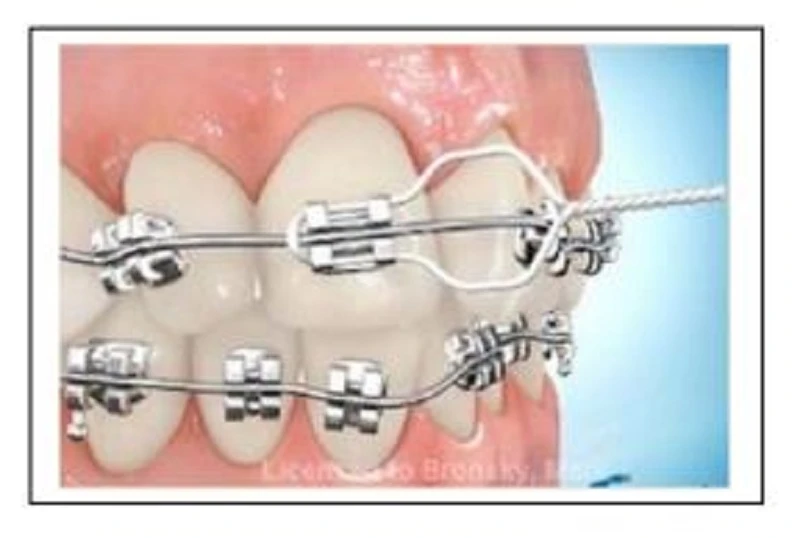

Dây cung 18X25 kích hoạt nhiệt (HANT) khi sử dụng mắc cài có thông số Li (lingual root torque) hoặc La (labial root torque). Dây cung này cần được làm lạnh hơn so với nhiệt độ trong miệng để làm nó “mềm hơn” và linh hoạt hơn để dễ đặt vào khe mắc cài. Tại nhiệt độ miệng, dây cung sẽ cứng lại, bắt đầu nhả lực lên răng. Dây cung này gần như luôn được sử dụng sau khi đặt dây 012N hoặc 014N được 2 tháng. Liên tục buộc dây vào mắc cài trong mỗi lần hẹn khoảng 6 tháng, cho đến khi dây nằm thụ động trong khe mắc cài và thay dây 19X25SS nếu có thể. Dây cung này cũng được sử dụng như dây cung “làm thẳng” đối với bộ răng hỗn hợp, có gắn band răng 6, gắn mắc cài các răng cửa trên, và dây cung sẽ đi qua các răng 6-2-2-6. Trong các trường hợp gần được Class I mà chen chúc, có thể chỉ cần dùng một dây 18X25HANT cho toàn bộ quá trình điều trị.

Dây cung này được “làm lạnh và buộc vào mắc cài” trong khoảng 4-6 tháng sau khi làm lỏng sơ khởi răng bằng dây Niti tròn. Trong suốt thời gian này, cần gắn lại mắc cài bị sai để mọi mắc cài đều được nằm ở vị trí đúng. Dây cung được giữ nguyên tại chỗ trong suốt thời gian điều trị này, không cần tháo khỏi miệng. Nếu dây cung được duy trì tại chỗ đủ lâu, thi sau đó có thể thay đây 19X25ss. Nếu bạn tháo bỏ dây 18X25 Hant và sau đó không thể mắc được dây 19X25ss, thì cần thay dây cung chuyển đổi, thường là dây 020ss trong 1 tháng trước khi đi đây 19X25SS.